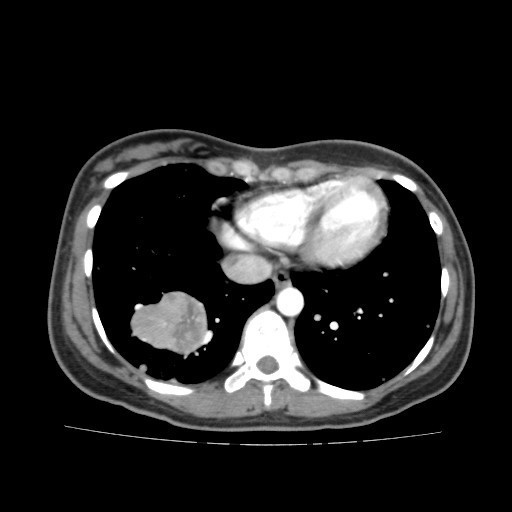

查体:右大腿上段较左侧增粗,后内侧皮下可触及大小约5*6cm肿物,质软,边界不清,活动度可,压痛(+),无波动感。 辅助检查:胸部CT:双肺多发转移瘤。

诊断:肺占位性病变(转移瘤?);大腿软组织疾患(右侧大腿肿物) 治疗:入院右下肢MR平扫+增强扫描:右侧大收肌软组织占位性病变,考虑间叶源性恶性肿瘤可能性大,血管源性可能?瘤周多发静脉曲张及侧枝循环形成,建议CT增强扫描进一步检查明确血管情况。遂于声引导下右大腿肿物穿刺活检,病理结果提示:(右大腿肿物)送检穿刺组织,肿瘤细胞形成器官样及腺泡状结构,细胞巢间为纤维性分隔,细胞呈大圆形、多边形,胞质丰富透亮,部分呈嗜伊红色,细胞核大,核分裂象少见,结合临床病史及免疫组化,考虑为腺泡状软组织肉瘤。免疫组化结果(①):CK(-),Vim(-),Ki-67(5%+),HMB45(-),MelanA(-),SMA(+),desmin(-),Myogenin(-),MyoD1(-),S100(-),NSE(部分+),CD56(-)。